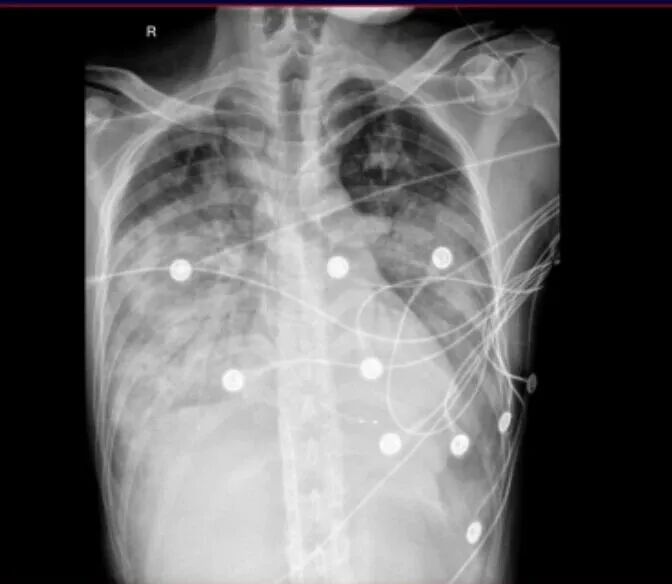

到院后,石聪辉主任带领急诊团队紧急查体,张先生呈端坐呼吸困难状态,虽然对答切题,但讲话断断续续,呼吸急促,口唇已经出现了紫绀(缺氧的典型表现),双肺能听到明显的湿性啰音(提示肺部有积液或炎症),心跳节律不齐。四肢末梢苍白、冰凉,这是休克的早期信号。

① 呼吸高达 38 次/分(正常成人仅 12-20 次/分);

② 血压 91/53 mmHg(还是在使用去甲肾上腺素升压的情况下,正常血压应 ≥ 90/60 mmHg);

③ 未吸氧时末梢血氧仅 65%(正常应 ≥ 95%,低于 80% 已属严重缺氧)。

情况危急!急诊科立即为他开通无创高流量吸氧,建立抢救通道,同时启动多学科协作(MDT)抢救。多学科专家会诊后,结合张先生的症状和检查结果,判断他病情危重,初步诊断为 「重症肺炎、急性心衰、心肌炎」,随即收入重症医学科(ICU)进一步治疗。